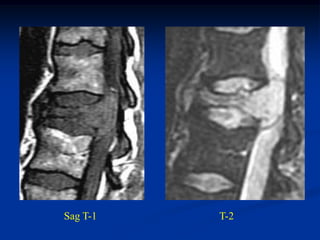

Case #1104.1                Chordoma L-1

49 year male with back

pain for 6 mos and recent

paraparesis

Sag T-1   T-2